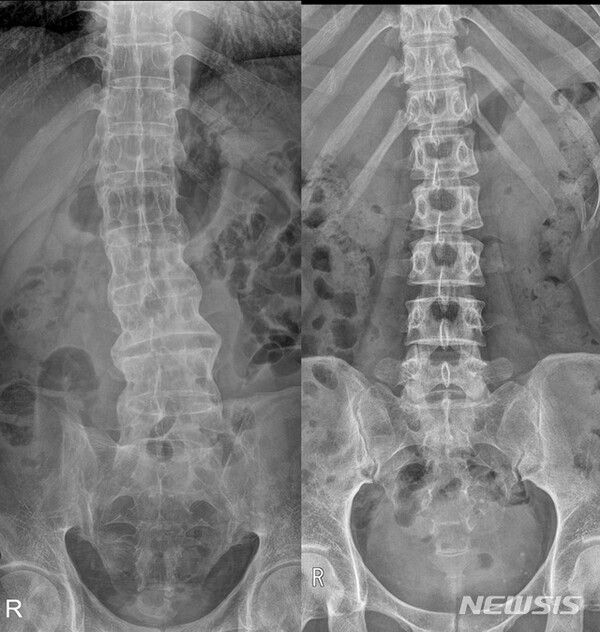

사진 = 뉴시스

장시간 앉아 있거나 아침에 일어났을 때 허리와 엉치 부위가 뻣뻣하고 통증이 느껴진다면 단순 요통이 아닌 '강직성 척추염'을 의심해 볼 필요가 있다.

뉴시스 보도에 따르면, 17일 의료계에 따르면 강직성 척추염은 척추와 천장관절 등 관절 부위에 만성적인 염증이 생겨 통증과 뻣뻣함을 유발하는 자가면역질환이다.